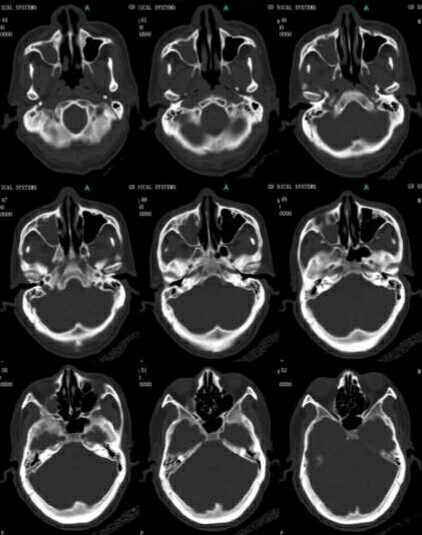

CT所见:鼻咽右侧顶壁、右侧咽隐窝软组织稍增厚,鼻咽左侧未见异常,双侧鼻咽旁间隙、颈动脉间隙未见异常。右侧上颌窦为软组织影充填,左侧上颌窦、筛窦、蝶窦未见异常。双侧乳突见软组织影,海绵窦未见异常。双眼未见异常。颅底未见骨质破坏。